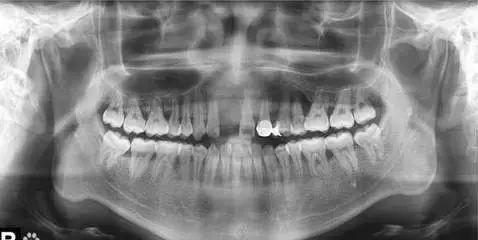

2.全口曲面断层片

曲面断层片放射剂量低,费用低,可提供全部牙齿的信息,广泛应用于临床,但其属于非定位拍摄,正畸治疗前后的时间间隔较长,很难保证相同的投射角度,以及放大率的不同,治疗前后牙齿位置的改变,均会造成牙齿长度测量的误差。曲面断层片与根尖片一样可以反映近远中向牙根吸收情况,但不能反映颊舌向的牙根吸收情况。